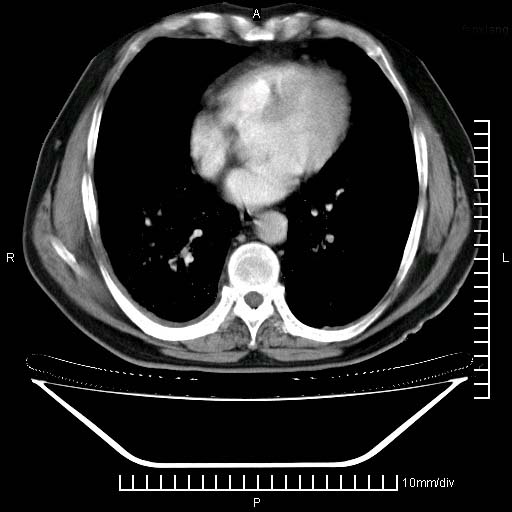

标题: CT24043:胸部增强:男性,60岁 [打印本页]

标题: CT24043:胸部增强:男性,60岁

既往肺结核,近10几天,咳嗽,咳痰,右侧胸痛,疼痛较明显,右上肺斑块考虑结核灶胸膜粘连,增强,可惜动脉期没有定好,未见强化,可延迟4分后又见较明显强化,中心见低密度影,如果说结核是边缘强化,可这个灶强化的面积挺大的,让人很挠头。

动脉期